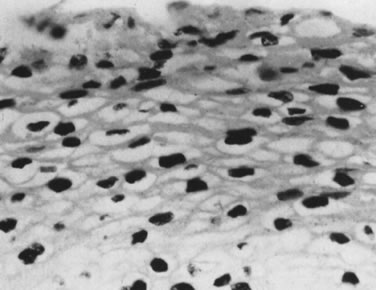

Sometimes, the virus-induced cellular changes are incomplete and focal. These histologic changes have been referred to as borderline koilocytotic atypia and are characterized by perinuclear cytoplasmic clearing, with mild to moderate variation in nuclear size in conjunction with hyperchromaticity and irregularity of the nuclear membranes68 (Fig. 7). Many of these epithelial changes probably represent nonspecific cellular reactions to inflammatory stimulants other than HPV.

Fig. 7. Epithelium with borderline koilocytotic atypia. Cytoplasmic clearing (perinuclear halos) is present, but the degree of atypia is minimal. The diagnosis of condyloma should not be made unless there is more variation in chromatin pattern and in nuclear size and contour. (Hematoxylin-eosin, ×500.)